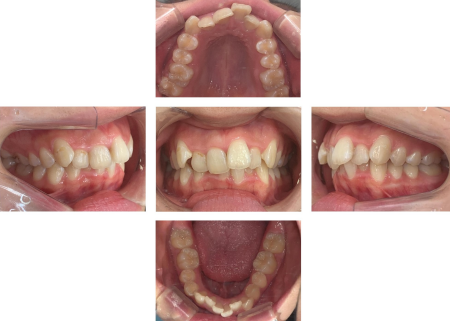

拝見すると、上下左右の前歯12本(中切歯/1番、側切歯/2番、犬歯/3番)が前後に重なり合っている「叢生(そうせい)」でした。

重なっている箇所やガタガタ具合が多いため、全体的に歯を動かしてきれいに並べることをご提案しました。